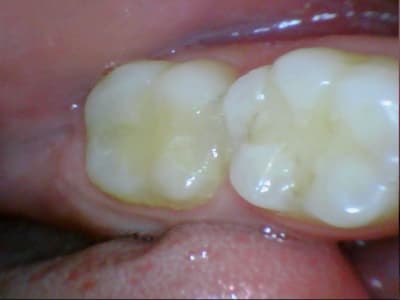

31/10/2011 à 18h09

tiens je me suis chronométré :)

28min :) lol

bon celui la etait un peu long, car provisoire collé au cvi cause durée avec le provisoire trop longue....

donc dur a déposer et obligé d'enlever les résidu de cvi aux US...

ceux qui font pas d'onlay vous proposez quoi là ?

patiente de 13 ans ...

Ca ressemble à un beau MIH avec un confrère qui a fait des trucs bizarres avec un amalgame.

Oui MIH déjà avec une belle récidive de carie. Je pense que dans un cas comme ça le compo est voué très vite à l’Échec...